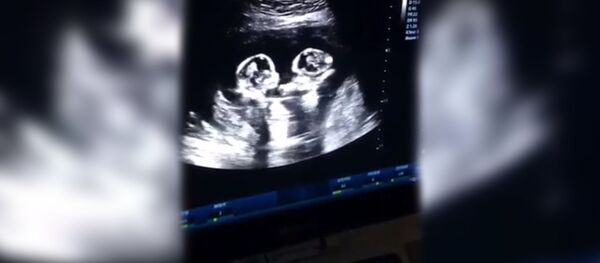

Ранее появились видеокадры "драки" сестер-близняшек в утробе матери, которые набрали более 2,5 миллиона лайков в Сети.